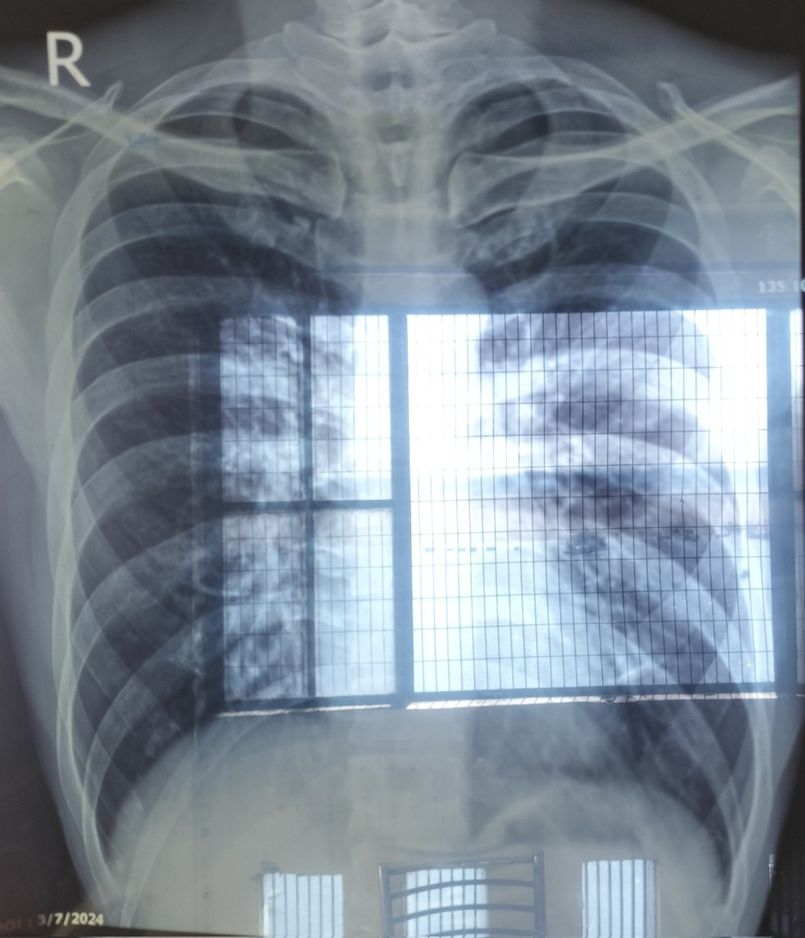

两人不久后出现剧烈发烧的情况,甚至严重到连站立和呼吸都感到痛苦,不得不紧急到瓦拉纳西当地医院求诊。住院4天期间身体极度虚弱,但院方准备的每一餐竟然都是咖哩,就连小食都是满满的香料,对于身体虚弱的他来说完全吃不下。

不仅如此,打点滴效果不好,他手臂肿得厉害。在蟑螂泛滥的病房住了4天,最终花费约152,980日圆(约7,470港元),没想到当初省下20卢比竟换来如此高昂的代价。